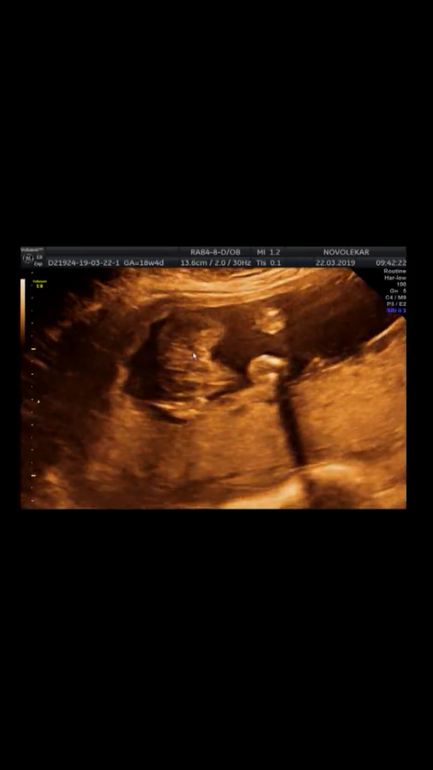

Добрый вечер)) сходили наконец на УЗИ, по УЗИ уже 19 неделек) чуть опережает. кто разбирается, подскажите на кого больше похоже?) спасибо)